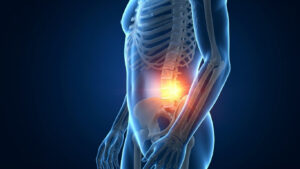

Η άσκηση με EMS βοηθά στην ενεργοποίηση βαθιών σταθεροποιητικών μυών που υποστηρίζουν τη σπονδυλική στήλη και τις αρθρώσεις.

Η βελτίωση της μυϊκής λειτουργίας συχνά συμβάλλει στη μείωση της επιβάρυνσης που δέχονται οι αρθρώσεις.